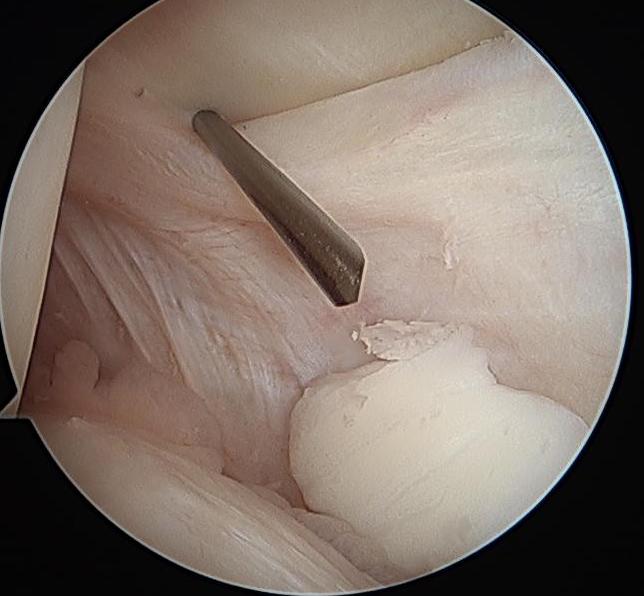

Tibial Tunnel

Incision medial to tibial tuberosity

- PCL jig inserted, usually set at 60 or 65o

- under fluoroscopy, identify the PCL facet

- at least 1 cm below the articular surface

- needs to be more lateral than medial to recreate the anterolateral bundle of PCL

- curette inserted to protect NV bundle

- knee in flexion to protect NV bundle

- beath pin passed

- ream appropriate tunnel (9 or 10 mm for achilles tendon allograft)

PCL tibial tunnelPCL DrillTibial Tunnel PCL